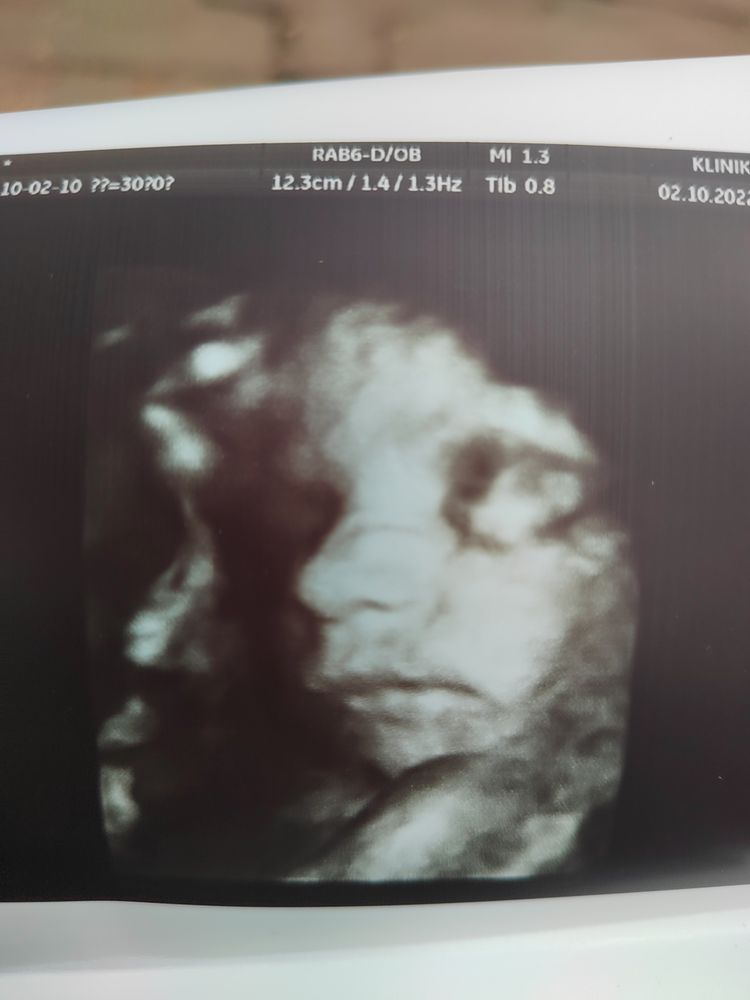

Всё о нашей беременностиНу вот я официально в декрете ) завтра буду спать ) сходили на узи с мужем .. Врач сказала все хорошо у нас )) но все размеры разные ) голова большая и я переживаю .. И она снова перевернулась и села на попу .. Доктор сказала, что голова и ноги в папу , он у нас высокий и умный ). У кого голова была больше срока?

Я после ковида всё переживала за плаценту, но врач сказал пока всё хорошо. Ну на 3 скрининге скажут какие размеры) Саша, а это УЗИ 3Д? Или так всё чётко видно на экране?

Полина , спасибо !я тоже эту неделю болела, тест не делала на ковид .. Поэтому сходили на узи .. Да 3д сделала врач мне на память ) а так я записалась на обычное узи , но мне она сделала как скрининг +3 д . голова у нас ещё на 1 скринине была больше

Полина , 1400 грамм озвучила ) сказала прибавка сейчас у малыша около 250 грамм в неделю будет

Аня

У сына в 30 недель была уже новорожденная голова 🙈 все хорошо) и у папы его она большая)

Мне тлже на 3 скрининге размер головы большой намерили, но мы скрининг повторяем, пойдем на узи в среду смотреть как там размеры у дочки. Вообще как я поняла все эти размеры относительны, мы тоже все разные поэтому дети все разные)

Jane, у нас и по первому скринингу тоже голова больше была изначально, я думала сравняется )) но видимо будет умная девочка ).. Мы почти купили все , кроме коляски и кокона ... Не могу определиться ..А так осталось все постирать , собрать кроватку , разложить все по сумкам в роддом ). Буду заниматься в декрете .. Я обещала на работе ещё 2 недели из дому поработать и потом все ).